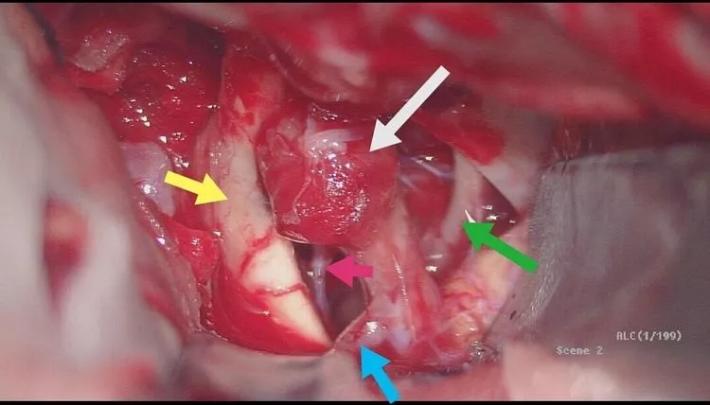

二次复合手术中DsA,黄箭→BBA,白箭→M1,绿箭→STA,M1由于痉挛与STA管径相当,病人有部分开放的前交通,所以本例我们采取的策略是①单支STA一M2搭桥②ICA颅外段阻断③BBA包裏夹闭or孤立④如包裏夹闭失败行孤立术则行STA一M2双支搭桥。

术中见颈动脉前壁局部为血块覆盖,分离血块見局部血管壁正常结构破坏,锐性分离显露BBA(白箭头),见瘤壁呈桑椹状外观,累及管壁周径约1/4~1/3,背侧lCA近瘤颈处发出脉前A(橙箭头),这个也是术中需要保护的功能血管,内侧视神经(黄箭头)与BBA粘连已松解,同侧A1(蓝箭头)显露充分,一旦BBA破裂可以阻断远端血流,提供清晰术野,动眼神经(绿箭头)位于视野外侧,充分显露可以减少术中神经血管副损伤,为包裹补片包绕BBA段提供操作空间!